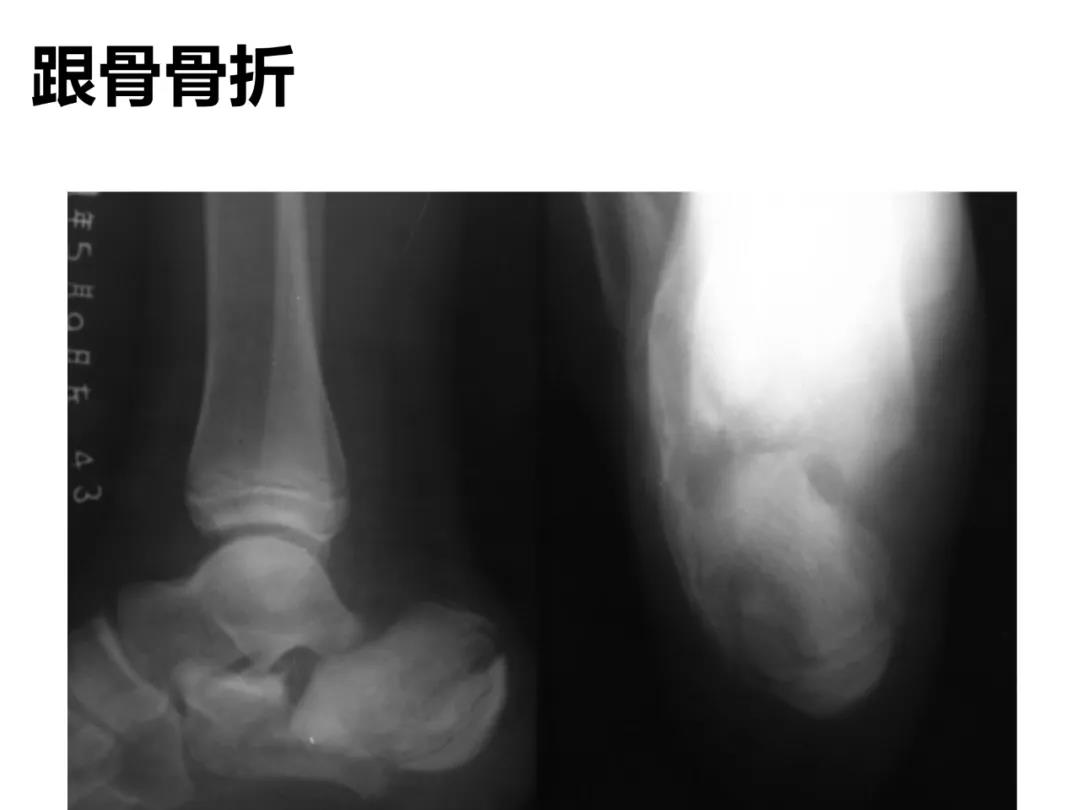

小儿骨科X线片汇总,临床读片宝典!